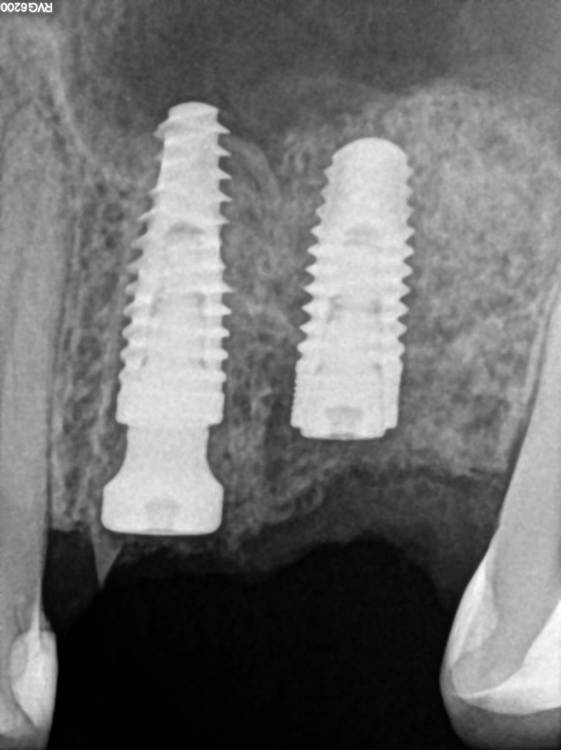

TIGER Опубликовано 8 мая, 2023 Автор Поделиться Опубликовано 8 мая, 2023 Всем привет!планировал удаление,но во время синуса решил использовать фрагмент как клин для стабилизации болта,в итоге совершил ошибку с более медиальной позицией 26,ибо шаблон не изготовил....через 5 мес одел времяхи,т.к будет тотал Ссылка на комментарий

Irouil Опубликовано 8 мая, 2023 Поделиться Опубликовано 8 мая, 2023 Вроде норм, в итоге 1 Ссылка на комментарий

TIGER Опубликовано 8 мая, 2023 Автор Поделиться Опубликовано 8 мая, 2023 @Irouil да,ортопедически всё отлично,я переживал Ссылка на комментарий